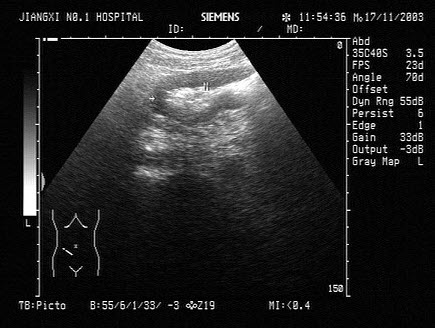

48、单项选择题

患者体检发现肝脏体积增大,超声见右叶巨大的强回声光团,边界见声晕,门脉见实质性光团充填,如图所示,考虑为()